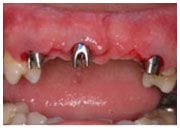

植牙過程

植入植體